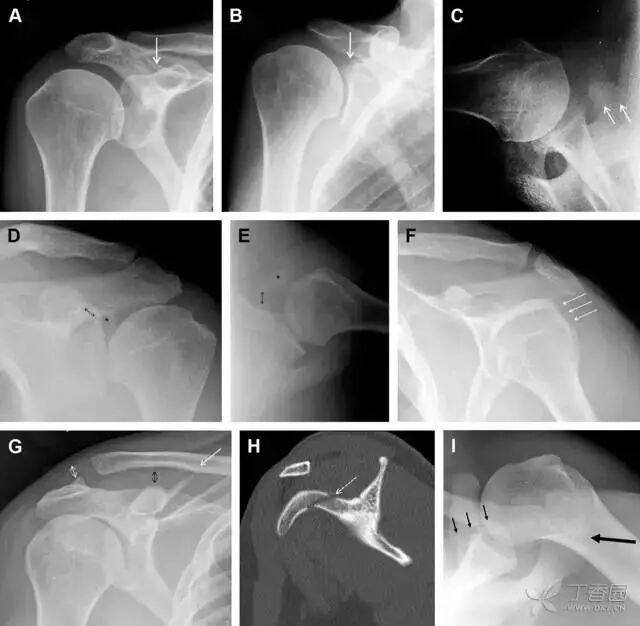

23单纯肱骨大结节骨折

与其它肱骨近端骨折不同,单纯肱骨大结节骨折常发生于年轻人。肱骨大结节骨折常由撞击或剪切/撕脱损伤所致:

撞击包括直接撞击、肩峰撞击、上关节盂撞击(极度外展时);

剪切/撕脱损伤常发生于肩关节前脱位。

在常规前后位片上,大结节与肱骨头重叠,骨折不易发现,外旋位前后位片有助于诊断。

图 1 大结节骨折。(A)脂肪抑制序列斜冠状位 MRI,显示肱骨大结节线性骨折无移位(箭头)与周围骨水肿;(B)外旋位前后位(AP)片,证实大结节骨折(箭头),典型的骨折愈合过程中的骨吸收表现;(C、D)初诊时内旋位、外旋位前后位片,初诊时漏诊,仔细回顾影像,内旋伞下可见双密度影(椭圆),骨皮质中断(箭头)

24无移位的桡骨头/颈骨折

多发生于摔倒时,手掌撑地,受到轴向、外翻应力所致。常规的前后位片容易漏诊,常需加拍内斜位、外斜位、桡骨头-肱骨小头位片。后脂肪垫可见(位于鹰嘴窝内,一般不可见)和/或前脂肪垫抬高常提示骨性损伤。

图 2 桡骨头骨折。前后位(A)和侧位(B)片示后脂肪垫抬高(黑色箭头),前脂肪垫抬高(白色箭头),呈「帆船征」,其它表现正常;外斜位(C)和桡骨头–肱骨小头位(D)示桡骨头关节内骨折线(虚线黑箭头)累及桡骨颈(虚线白箭头)

25肩胛骨骨折

肩胛骨几何形状复杂,受到邻近其它骨性结重叠阻挡,且肩胛骨骨折少见,因此容易漏诊。当存在解剖变异时,诊断更为困难。

图 3 肩胛骨骨折正侧位片:由于骨块的叠加,(A)前后位片示「V」形高密度影(*),肩胛颈下方可见骨皮质碎片(箭头);(B)侧位片示骨皮质中断,骨折段移位,但由于肱骨的重叠遮挡,决断往往比较困难

26喙突骨折

喙突骨折可发生于直接暴力、肩关节脱位过程的肱骨头撞击、以及撕脱骨折(肱二头肌短头、喙肱肌)。

其中喙突基底部骨折最多见,常发生于直接暴力或肱骨头前脱位,骨折可延伸至关节盂。

而撕脱骨折多为喙突尖部的骨折。需要加拍腋位和 Stryker 位片(X 射线束以喙突为中心并头倾 10°,手臂外展,这样可以避开骨性结构的阻挡)。

有时,负重位片可发现并存的肩锁关节脱位,将有助于诊断。

图 4 喙突骨折。66 岁男性患者,猎枪射击后右肩前方疼痛。(A)内旋位前后位片投影隐约可见喙突基底部骨折(白色箭头),(B)外旋位前后位片投影结构存在重叠,(C)腋位投影时可良好显示。(D~F)喙突骨折伴 Hill-Sachs 损伤:肩关节脱位后慢性疼痛,喙突骨折块(*)向前外侧移位(双箭头),在外旋前后位(D)及腋位(E)片上均可显示,在内旋位前后位(F)片上,喙突被遮挡,但可见肱骨头 Hill-Sachs 损伤。(G、H)喙突骨折伴肩锁关节脱位,肩锁关节分离(白色双箭头),而喙锁间距正常(黑色的双箭头),应警惕喙突骨折。(I)喙突与肩峰骨化中心:对于未成年人,喙突与肩峰骨化中心可同时存在,易与骨折混淆,此时,拍对侧的 X 线片对比将有助于诊断。

27肩峰骨折

肩峰骨折为高能量损伤,多由直接暴力导致,好发于中青年患者,多伴有肩关节其它结构损伤。有必要拍摄 Rockwood 位(前后位片,X 线束尾倾),特别有利于显示肩峰下部及肩峰下间隙。

图 5 肩峰骨折。内旋位前后位(A)片上,骨折线几乎被喙突完全遮挡, 但是在标准前后位(B)和腋位(C)片上可见骨折线

28骨折伴盂肱关节不稳

肩关节是最容易脱位的关节之一,肩关节脱位常伴随其它结构的损伤,如血管神经损伤、肩袖损伤、盂唇损伤、Bankart 损伤等。脱位本身诊断往往是明确的,容易被忽略的是其继发的伴随损伤。

需要仔细评估肱骨头、大结节、关节盂边缘、肩峰、喙突等结构。典型的 X 线投射角度包括:内旋位前后位片、外旋位前后位片(Grashey 位)、侧位(肩胛骨 Y 位)、腋位片以及改良腋位片。

图 6 肩关节前脱位伴有 Hill–Sachs 和 Bankart 损伤:(A~C)肱骨头后外侧撞击骨折,白色箭头所示为骨折的内侧边界;(A)内旋位前后位片,(B)「V」形压缩骨折的下边界(虚线短箭头),(C)Garth 位(轴向投影)示 Hill–Sachs 损伤(虚线和实线折箭头),特别是对骨性 Bankart 损伤的诊断有帮助。(D、E)MRI 进一步证实了损伤

图 7 肩关节后脱位伴有反 Hill–Sachs 损伤。(A)外旋位前后位片可见一硬化带(黑箭头),此「凹槽征」与肱骨头关节面平行;(B)腋位片进一步证实了骨折的存在

29Essex-Lopresti 损伤

Essex-Lopresti 损伤是桡骨头骨折伴有下尺桡关节脱位,导致骨间膜损伤,桡骨短缩。此种损伤,桡骨头骨折的诊断往往是明确的,容易忽视的是下尺桡关节脱位,特别是早期,下尺桡关节的症状不明显,X 线表示也不明显。

图 8 Essex-Lopresti 损伤。前后位(A)和侧位(B)示桡骨头关节内骨折(白色实线箭头);(C~E)伤后 1 个月复诊,患者诉腕关节疼痛,X 线(C,D)发现下尺桡关节脱位,(E)CT 进一步证实损伤的存在